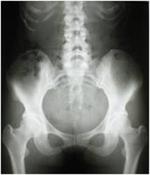

骨盤から腰椎にかけてのレントゲン画像。腰痛の原因評価に使われる骨格の状態。

• レントゲン検査